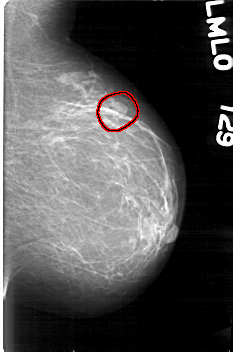

FILE: D_4045_1.LEFT_CC.OVERLAY

TOTAL_ABNORMALITIES 1

ABNORMALITY 1

LESION_TYPE MASS SHAPE LOBULATED MARGINS OBSCURED

ASSESSMENT 0

SUBTLETY 3

PATHOLOGY BENIGN

TOTAL_OUTLINES 2

BOUNDARY